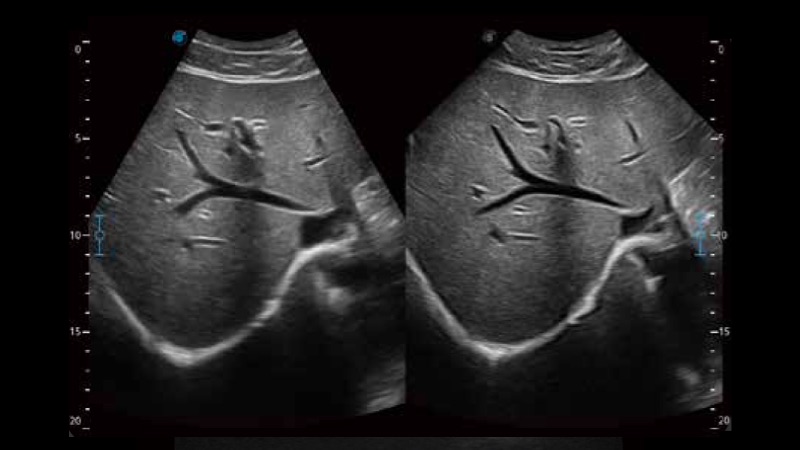

扩展成像技术

凸阵、线阵和相控阵探头进行实时扫描时,开启扩展成像模式,可以扩展超声图像视野,以便更完整地查看大的病灶或组织器官的解剖结构。

实时宽景成像技术

通过彩色血流和实时宽景相结合,可观察到完整的动静脉血流,方便医生检查。实时扫查过程中,如有任何操作失误也可以很容易地进行回扫擦除,而不会中断扫查。

临床图像